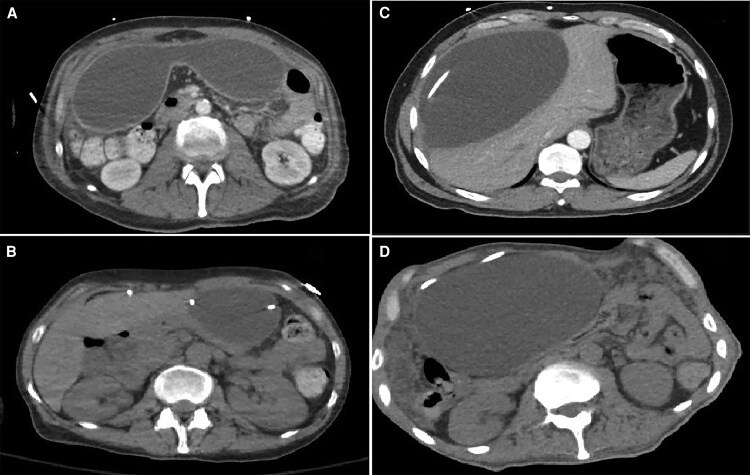

图示:球粒性脑膜炎伴脑室-腹膜分流的腹部假性囊肿。

脑室-腹膜(VP)分流是难治性球粒性脑膜炎(CM)相关脑积水患者脑脊液分流的主要方法。腹部假性囊肿(APCs)是一种罕见但已知的远端分流导管并发症,在CM中尚未得到很好的描述。我们对2010年至2024年间接受VP分流术的124例CM患者进行了回顾性研究。21例(17%)患者出现apc,大多数患者表现为分流管功能障碍症状,而不是腹部不适。这一发生率明显高于先前报道的由其他病因引起的脑积水患者。71%的患者存在活动性球虫感染的证据。成像通常显示远端导管尖端积液,大多数患者接受了针对远端分流的手术干预。尽管进行了干预,但仍有相当大的比例发生了反复的分流故障。这些发现补充了CM中APCs的有限文献,并可能为其表现、影响因素和管理的未来研究提供信息。

Ventriculoperitoneal (VP) shunts are the mainstay for cerebrospinal fluid diversion in patients with refractory coccidioidal meningitis (CM)-associated hydrocephalus. Abdominal pseudocysts (APCs), an uncommon but known complication of distal shunt catheters, have not been well described in CM. We conducted a retrospective study of 124 patients with CM who underwent VP shunt placement between 2010 and 2024. APCs occurred in 21 patients (17%), with most presenting with symptoms of shunt malfunction rather than abdominal complaints. This incidence is notably higher than previously reported in patients with hydrocephalus due to other etiologies. Evidence of active Coccidioides infection was present in 71% of patients. Imaging typically revealed fluid collections at the distal catheter tip, and most patients underwent surgical intervention targeting the distal shunt. Despite intervention, recurrent shunt failures occurred in a substantial proportion. These findings add to the limited literature on APCs in CM and may inform future research into their presentation, contributing factors, and management.